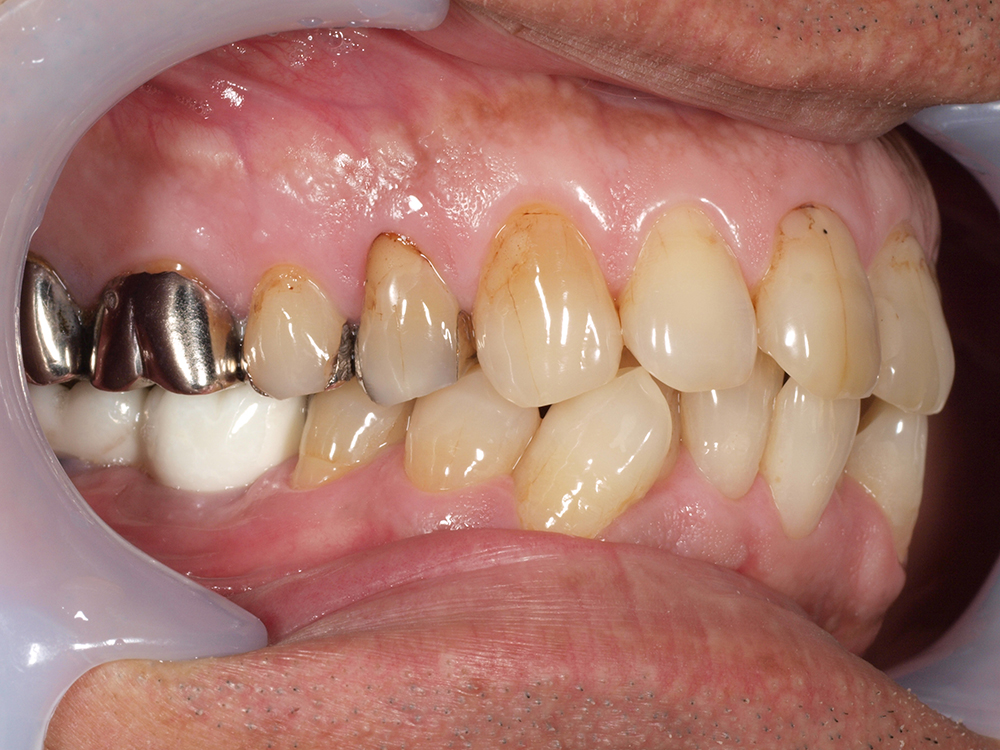

58歳 女性 歯科大学病院 教授からの紹介。

- 主訴

- 左下6番目、右上4番目の歯が長期にわたり痛く、噛めない、

- 処置内容

-

2本インプラント埋入+再生処置。抜歯即時埋入、⇒抜歯を行い、同時にインプラント埋入(即時埋入)

矯正処置

- 治療費用

- 上顎、下顎共に、約40万円(税込)(合計約80万円(税込))

- 治療期間

- 下顎:約6か月、上顎:約9か月

- リスク

- 上部構造物、仮歯の破折、術後の腫れ(3日)、人工歯根脱落リスクがあります

- その他

- 歯科大学病院 教授からの紹介。